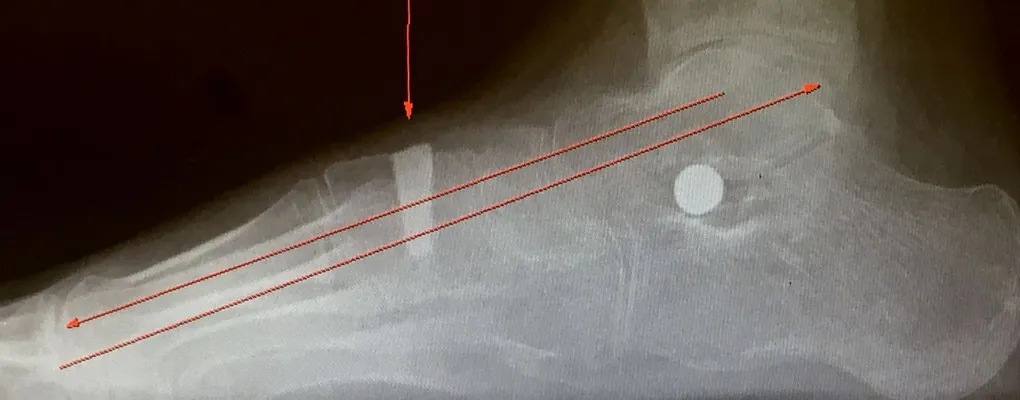

Pre-operative x-rays of the flatfoot with the talus deviated medially due to subluxing off the calcaneus causing the midtarsal joint to sublux laterally and uncovering of the talar head at the talo-navicular joint (left). The talus bone should line up with or be close to paralletl with a line drawn through the 1st metatarsal shaft (right). This is referred to as Meary's angle.

One case see an improvement in Meary's angle after surgical repair of the flatfoot with a subtalar joint implant which blocks the subluxation of the talus off of the calcaneus.